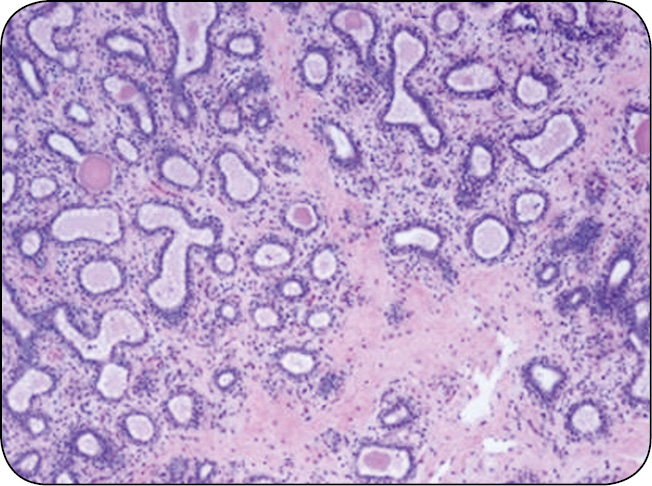

Czas od zakończenia laktacji do porodu to okres zasuszenia. U krowy trwa on przeważnie od 30 do 80 dni, zwykle 40-60 dni. W tym okresie poza przygotowaniem organizmu do zbliżającego się porodu tkanka gruczołu mlekowego ulega przemianom. Przebudowa tkanki wydzielniczej gruczołu mlekowego (inwolucja i ewolucja) odbywa się w trzech etapach. Pierwszy trwa 2-3 tygodnie i charakteryzuje się ograniczeniem zdolności komórek wydzielniczych do syntezy i sekrecji mleka oraz ich apoptozą. Druga faza – to trwający 3-4 tygodnie odpoczynek tkanki gruczołowej, kiedy ma miejsce pełne zasuszenie. W trzeciej fazie zachodzi ponowny rozwój tkanki wydzielniczej. W tej fazie, która przypada na ostatnie 2 tygodnie ciąży, nabłonek gruczołowy ulega proliferacji oraz dyferencjacji, czego konsekwencją jest produkcja siary, a po porodzie – mleka. W pierwszej i trzeciej fazie okresu zasuszenia, kiedy tkanka wymienia podlega intensywnej przebudowie, najczęściej dochodzi do zakażeń gruczołu mlekowego (ryc. 1, s. 43).